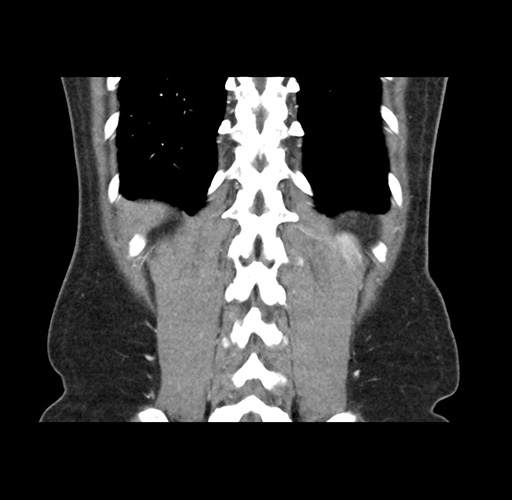

Imaging Analysis

Look through the patient's CT scan to identify any areas of concern for the necessary procedure.

Based on your CT findings, which issue(s) would give reason for "planned slowing down moment(s)" in this case?